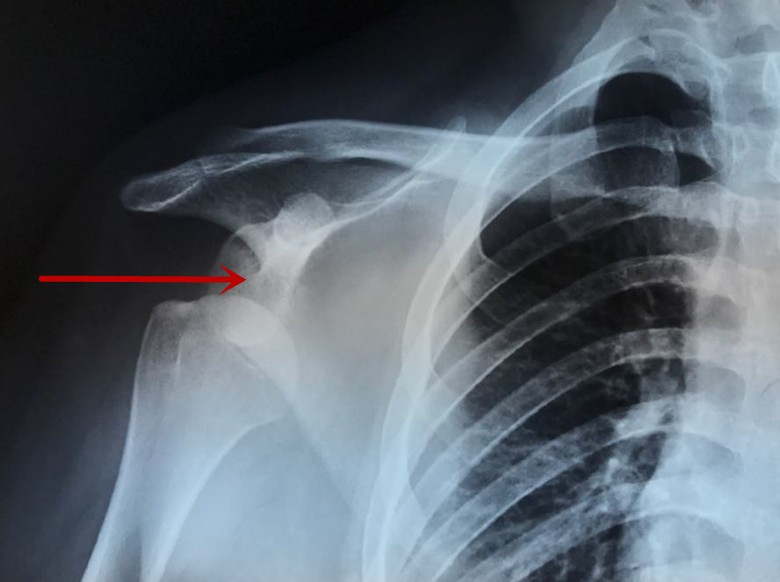

图上红色箭头标识的部位就是正常肩锁关节,平平的,没有受外伤不会翘起来。而上图中盂肱关节就是我们平常所说的肩关节,肩关节是人体活动度最大的关节,也最容易脱位,下图就是肩关节脱位的X线片。但是,肩关节脱位的畸形并不会让然感觉肩膀翘起来,而是感觉肩膀不能动了。